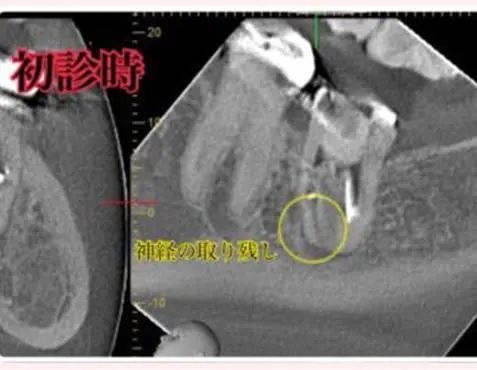

診断:CTによる精密検査で見つかった複雑な感染源

CTでしっかりと診断を行ったところ、とても深刻な状況でした。根管治療が重要ですが、それだけでは完全な治癒が望めない場合もあり、歯槽骨の再生を促す外科的処置が必要になることもあります。

こちらの患者様のように、歯槽骨のダメージが大きい症例では、根管内の感染と歯肉溝内の感染が両方の原因となっていることが多いですね。

EDTA、次亜塩素酸、クエン酸などの消毒液を使用して、根管内を隅々まで徹底的に消毒を行い、根管内の残存歯髄も完全に取り除かなければ、二次感染のリスクが残りますので、それを十分に注意する必要があります。そこで、マイクロスコープを使用し、肉眼では見えない細かい部分まで確認しながら治療を進めました。